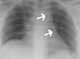

Catheter malposition